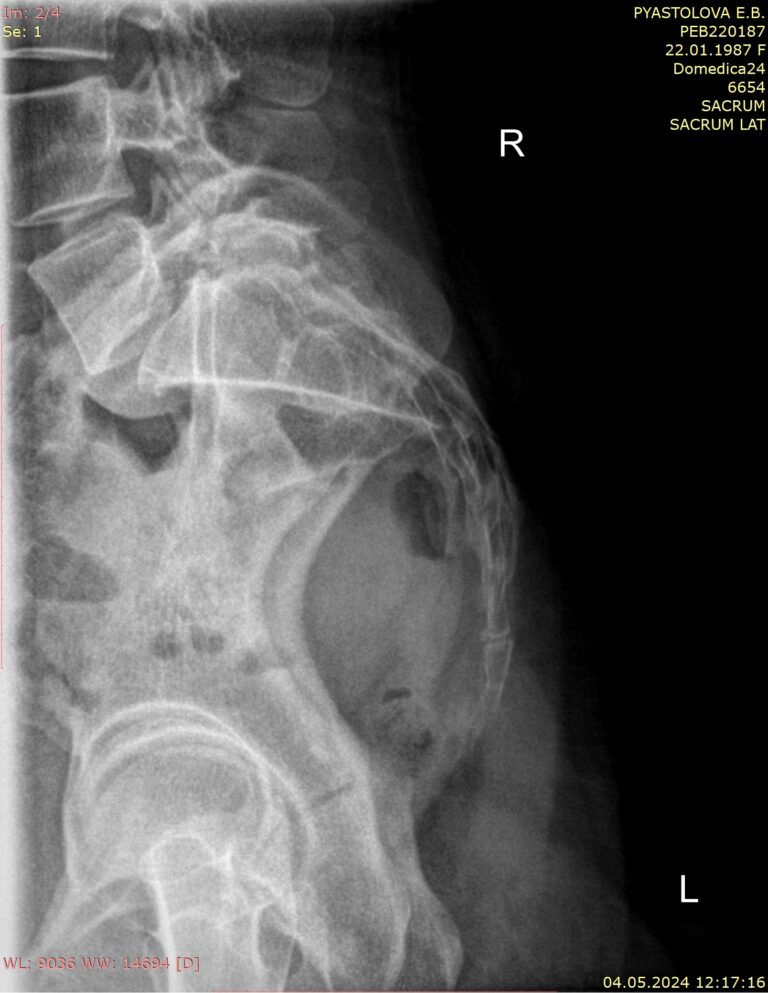

На снимках сравнивается положение копчика сидя и стоя. Для этого врач определяет (чертит) на снимках крестцово-копчиковый угол, который в норме составляет около 150о. Также проводится дугообразная линия через центр копчиковых позвонков:

• Здоровый копчик отклоняется кпереди или кзади на 5-20о или примерно 2 см при сидении и возвращается обратно при стоянии;

• При гипермобильности, посттравматической или идиопатической, то есть ни с чем не связанной, отклонение будет чрезмерным ― больше 25о. А сам угол при этом уменьшается от 140 до 90о;

• При подвывихе происходит смещение сегмента копчика кзади или кпереди, на дугообразной линии видна ступенька;

• При сращении с крестцом копчик будет неподвижен ― неизменен на обеих рентгенограммах;

• Также на снимке могут быть видны: переломы, новообразования, костные разрастания, отек мягких тканей.

Выполняется 2 теста:

• В положении сидя боком к экрану;

• В положении стоя, так же боком, то есть в обычной боковой проекции. Иногда этот снимок выполняется, когда пациент лежит.